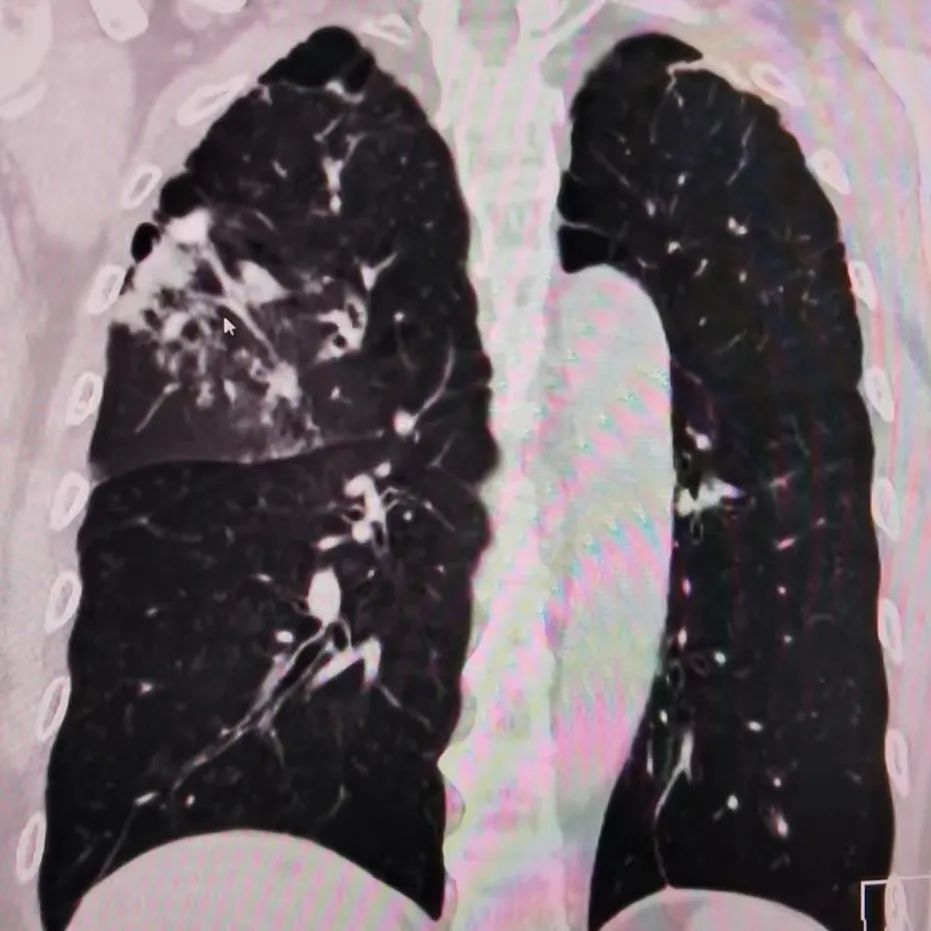

右肺上叶的病灶

肺动脉CTA及主动脉CTA检查后,排除了肺动脉栓塞及肺动脉瘤,发现了异常迂曲、增粗的右支气管动脉。屏幕上显示患者的肺内多发斑片状渗出影,较前一日CT明显加重,且肺内伴有肺血坠积,一切都提示着介入造影的必要性。面对家属的迟疑,介入科倪志华主任详细讲解了介入治疗的必要性及操作过程中避免并发症的举措,终于打消了该家属的顾虑。

当晚20点30分,患者进入DSA室,正式开始医院第一例支气管动脉栓塞术。手术过程顺利,咯血原因被很快找到,罪魁祸首是右肺上叶肺动脉分支处的一个动静脉瘘(支气管动脉-肺动脉分支瘘)。由于动静脉瘘再次发生大咯血的概率极大,甚至会威胁生命,所以此次介入手术可谓“一场及时雨”。